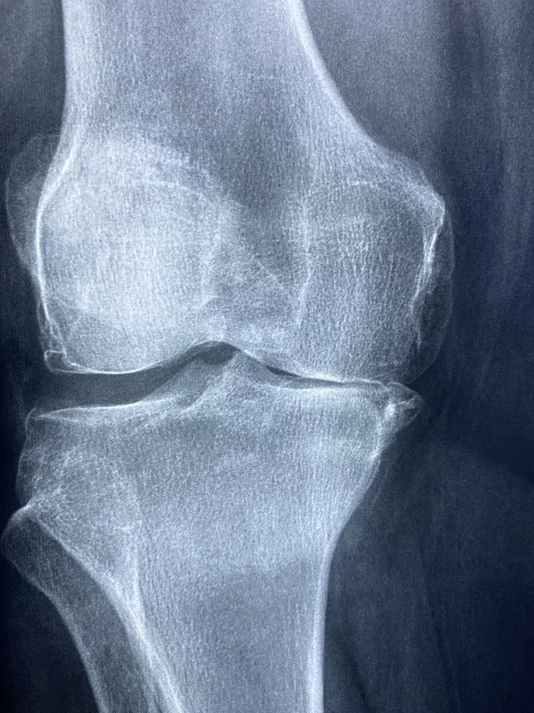

퇴행성 관절염 증상

퇴행성 관절염(골관절염) 증상을 알아봄으로써 초기에 진단하여 조기에 완치하여 우리 삶의 질을 높여보도록

하세요. 퇴행성 관절염은 전신적인 증상을 호소하는 류머티즘 관절염과 다른 것은 퇴행성 관절염은 초기에 호소되는 증상은 국소적인 통증이라는 점입니다. 퇴행성 관절염 증상은 특별한 기질적인 원인이 없이 나이, 성별, 유전적인 요인 등에 따라 발생하는 특발성 관절염과 관절 연골에 손상을 줄 수 있는 외상, 질병 및 기형 등이 원인이 되어 발생하는

이차성 또는 속발성 관절염등으로 분류되어집니다. 관절을 보호하고 있는 연골의 손상이나 퇴행성 변화로

인해 관절을 이루는 뼈와 손상이 생겨 염증과 통증이 발생하는 질환입니다.

2. 퇴행성 관절염 증상

퇴행선 관절염 증상은 관절 부위의 국소적인 통증이며 초기에는 관절을 움직일 때 심해지는 양상을 보이다가 병이

진행되면 움직임 여부에 관계없이 지속적으로 나타나기도 합니다.

관절 운동 범위의 감소,종창(부종),관절 주위의 압통이 나타나면 관절 연골의 소실과 변성에 의해 관절면이 불규칙해지면 관절 운동 시 마찰음이 느껴질 수 있습니다.

1)무릅관절에 발생할 경우 관절 모양과 변형과 함께 걸음걸이에 이상을 보일 수 있습니다.